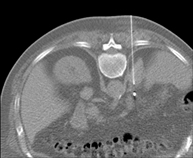

- CT-guided abdominal FNA (fine needle aspiration)

It consists in obtaining a tissue sample from a specific lesion located in the abdominal cavity. This test is performed using local anaesthesia on the puncture area, which is administered with fine-gauge needles. The entire procedure is monitored using images obtained by computed tomography (CT) at various stages of the puncture, using fluoroscopy-CT equipment. After the test, the patient remains under observation in hospital for a few hours. Coagulation tests must be performed before the puncture.

- CT-guided abdominal biopsy

It consists in obtaining a tissue sample from a specific lesion located in the abdominal cavity. It is sometimes performed under sedation with the help of an anaesthesia team. Needles are used to draw a cylinder sample from the lesion to be studied, which is then sent to the Pathology Department for histological analysis. The entire procedure is monitored using images obtained by computed tomography (CT) at various stages of the biopsy, using CT fluoroscopy. After the test, the patient remains in hospital under observation. Coagulation tests must be performed before the puncture.

- CT-guided abdominal drainage (abscesses, collections)

It consists of placing a drainage catheter over a collection of fluid located in the abdominal cavity, with the intention of emptying as much of the collection as possible. The patient should keep the drain in place for a few days, usually until it is no longer productive. It is often performed under sedation with the help of an anaesthesia team. The entire procedure is monitored using images obtained by computed tomography (CT) at various stages of the test, using CT fluoroscopy. After the test, the patient remains hospitalised. Coagulation tests must be performed before the test.